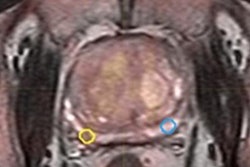

Abreu-Gomez and colleagues retrieved T2-weighted, diffusion-weighed (DWI), and dynamic contrast-enhanced images to evaluate the compliance with technical specifications at four referral facilities that house five 1.5-tesla MRI systems and one tertiary care referral facility with a 3-tesla system. The director of prostate imaging at the tertiary care referral center initially reviewed the performance specifications of each of the five MRI systems to create a baseline and then sent an itemized list to each site with the necessary technical modifications required to achieve PI-RADS v2 compliance.